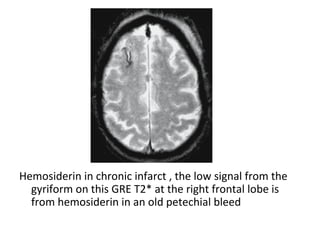

Hemosiderin in chronic infarct , the low signal from the

gyriform on this GRE T2* at the right frontal lobe is

from hemosiderin in an old petechial bleed